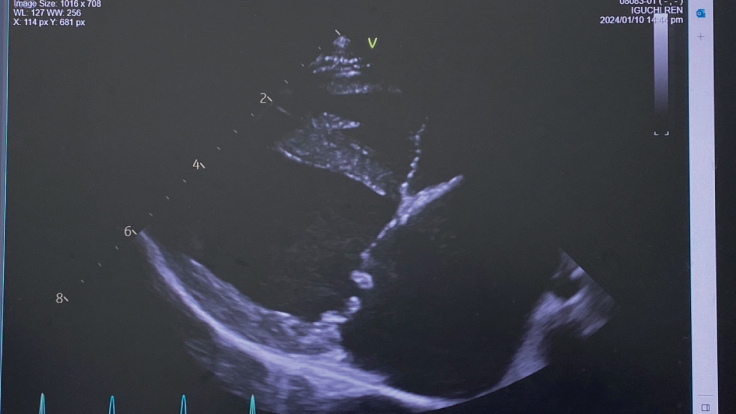

≪僧帽弁閉鎖不全症とは?≫

心臓内の弁膜に病変が起こり、うまく閉じなくなる事で心臓の血流が悪くなる(逆流)が起こる病気です。

この病気は通常ゆっくりと進行して弁膜を支えている腱が切れていくため徐々に逆流量が増え、結果と

して心臓は徐々に肥大し肺に水が溜まるのが肺水腫です。

心臓が負担に耐えられなくなると心不全を引き起こします。一般的に認められる症状は咳、疲れやすい

呼吸困難、失神などで日常生活に支障をきたし生命を脅かす事もあります。

心臓内の弁膜が正常に閉じていないことで

血流が逆流してします。

※動物病院にて掲載の許諾を得ております。

レンの僧帽弁閉鎖不全症は、重度のステージCです。